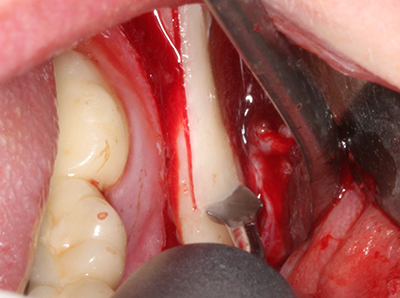

When surgical procedures are performed on bone in the immediate vicinity of sensitive structures such as blood vessels or nerves, rotary instruments pose a significant risk of iatrogenic injury. Piezoelectric devices can be helpful for preparation of bone covers and removal of hard tissue close to nerves, particularly for exposure of nerves after iatrogenic injury but also during nerve lateralization for resective and reconstructive procedures or implant placement (Fig. 17-20). Light contact between the piezotip and the nerve does not generally result in damage but proceeding incautiously with saw-like motions or attachments where a residual bone substrate remains may cause temporary or even permanent nerve damage. However, the risk of damage is considered to be substantially lower than when using saws or milling instruments (Pereira, Gealh et al. 2014).

Indication: Preparations close to nerve tissue

As noted above, indications for piezo surgery can also be found in the field of conservative dental surgery. Special working tips simplify the exposure of root tips and make it easier to protect nerves and sinus mucous membranes, particularly in the lower premolar and upper posterior tooth regions. Angled diamond tips are used to precisely prepare the resection cavity for the retrograde root filler material for unsealed apical obturation. The ultrasonic technology means the tips can be very slender, which improves the view and the size of the access cavity. As a result, the application of ultrasonic surgery for this indication is one of the standard procedures for apical resection (Del Fabbro, Tsesis et al. 2010, Scarano, Artese et al. 2012).